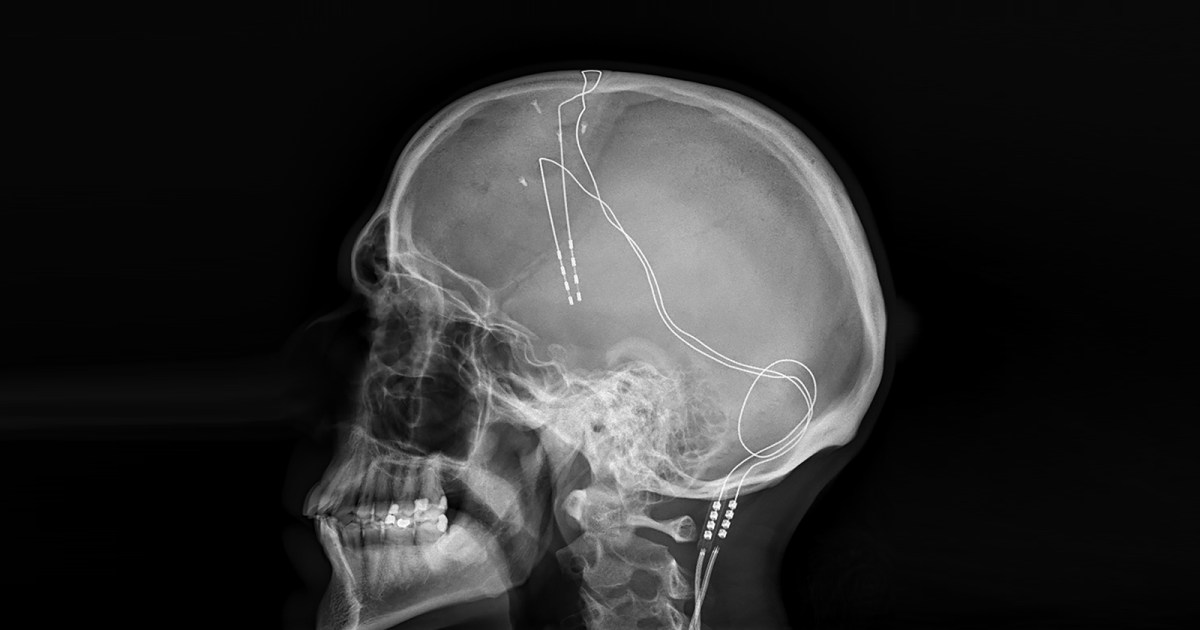

Aby przeprowadzić leczenie, chirurg wszczepia jedną lub więcej elektrod do mózgu pacjenta. Mały, zasilany bateryjnie generator impulsów, zwykle umieszczany pod skórą w pobliżu obojczyka pacjenta, następnie wysyła prąd elektryczny do elektrod za pomocą wszczepionego drutu.

Został zaprojektowany tak, aby naturalne napełnienie płuc wywierało nacisk na wszczepiony „nanogenerator”, który przekształca ruch w elektryczność statyczną. Prąd z nanogeneratora ładuje a super kondensatorktóry następnie włącza głęboki stymulator mózgu.

Do wyświetlenia urządzenia użyto „symulowanej świni”, składającej się z prawdziwych świńskich płuc wewnątrz sztucznej ludzkiej klatki piersiowej. Kiedy płuca świń zostały napompowane pompą, ruch ten generował wystarczającą ilość energii, aby superkondensator poza żebrami uderzył w stymulator głębokiego mózgu 60 razy na sekundę.